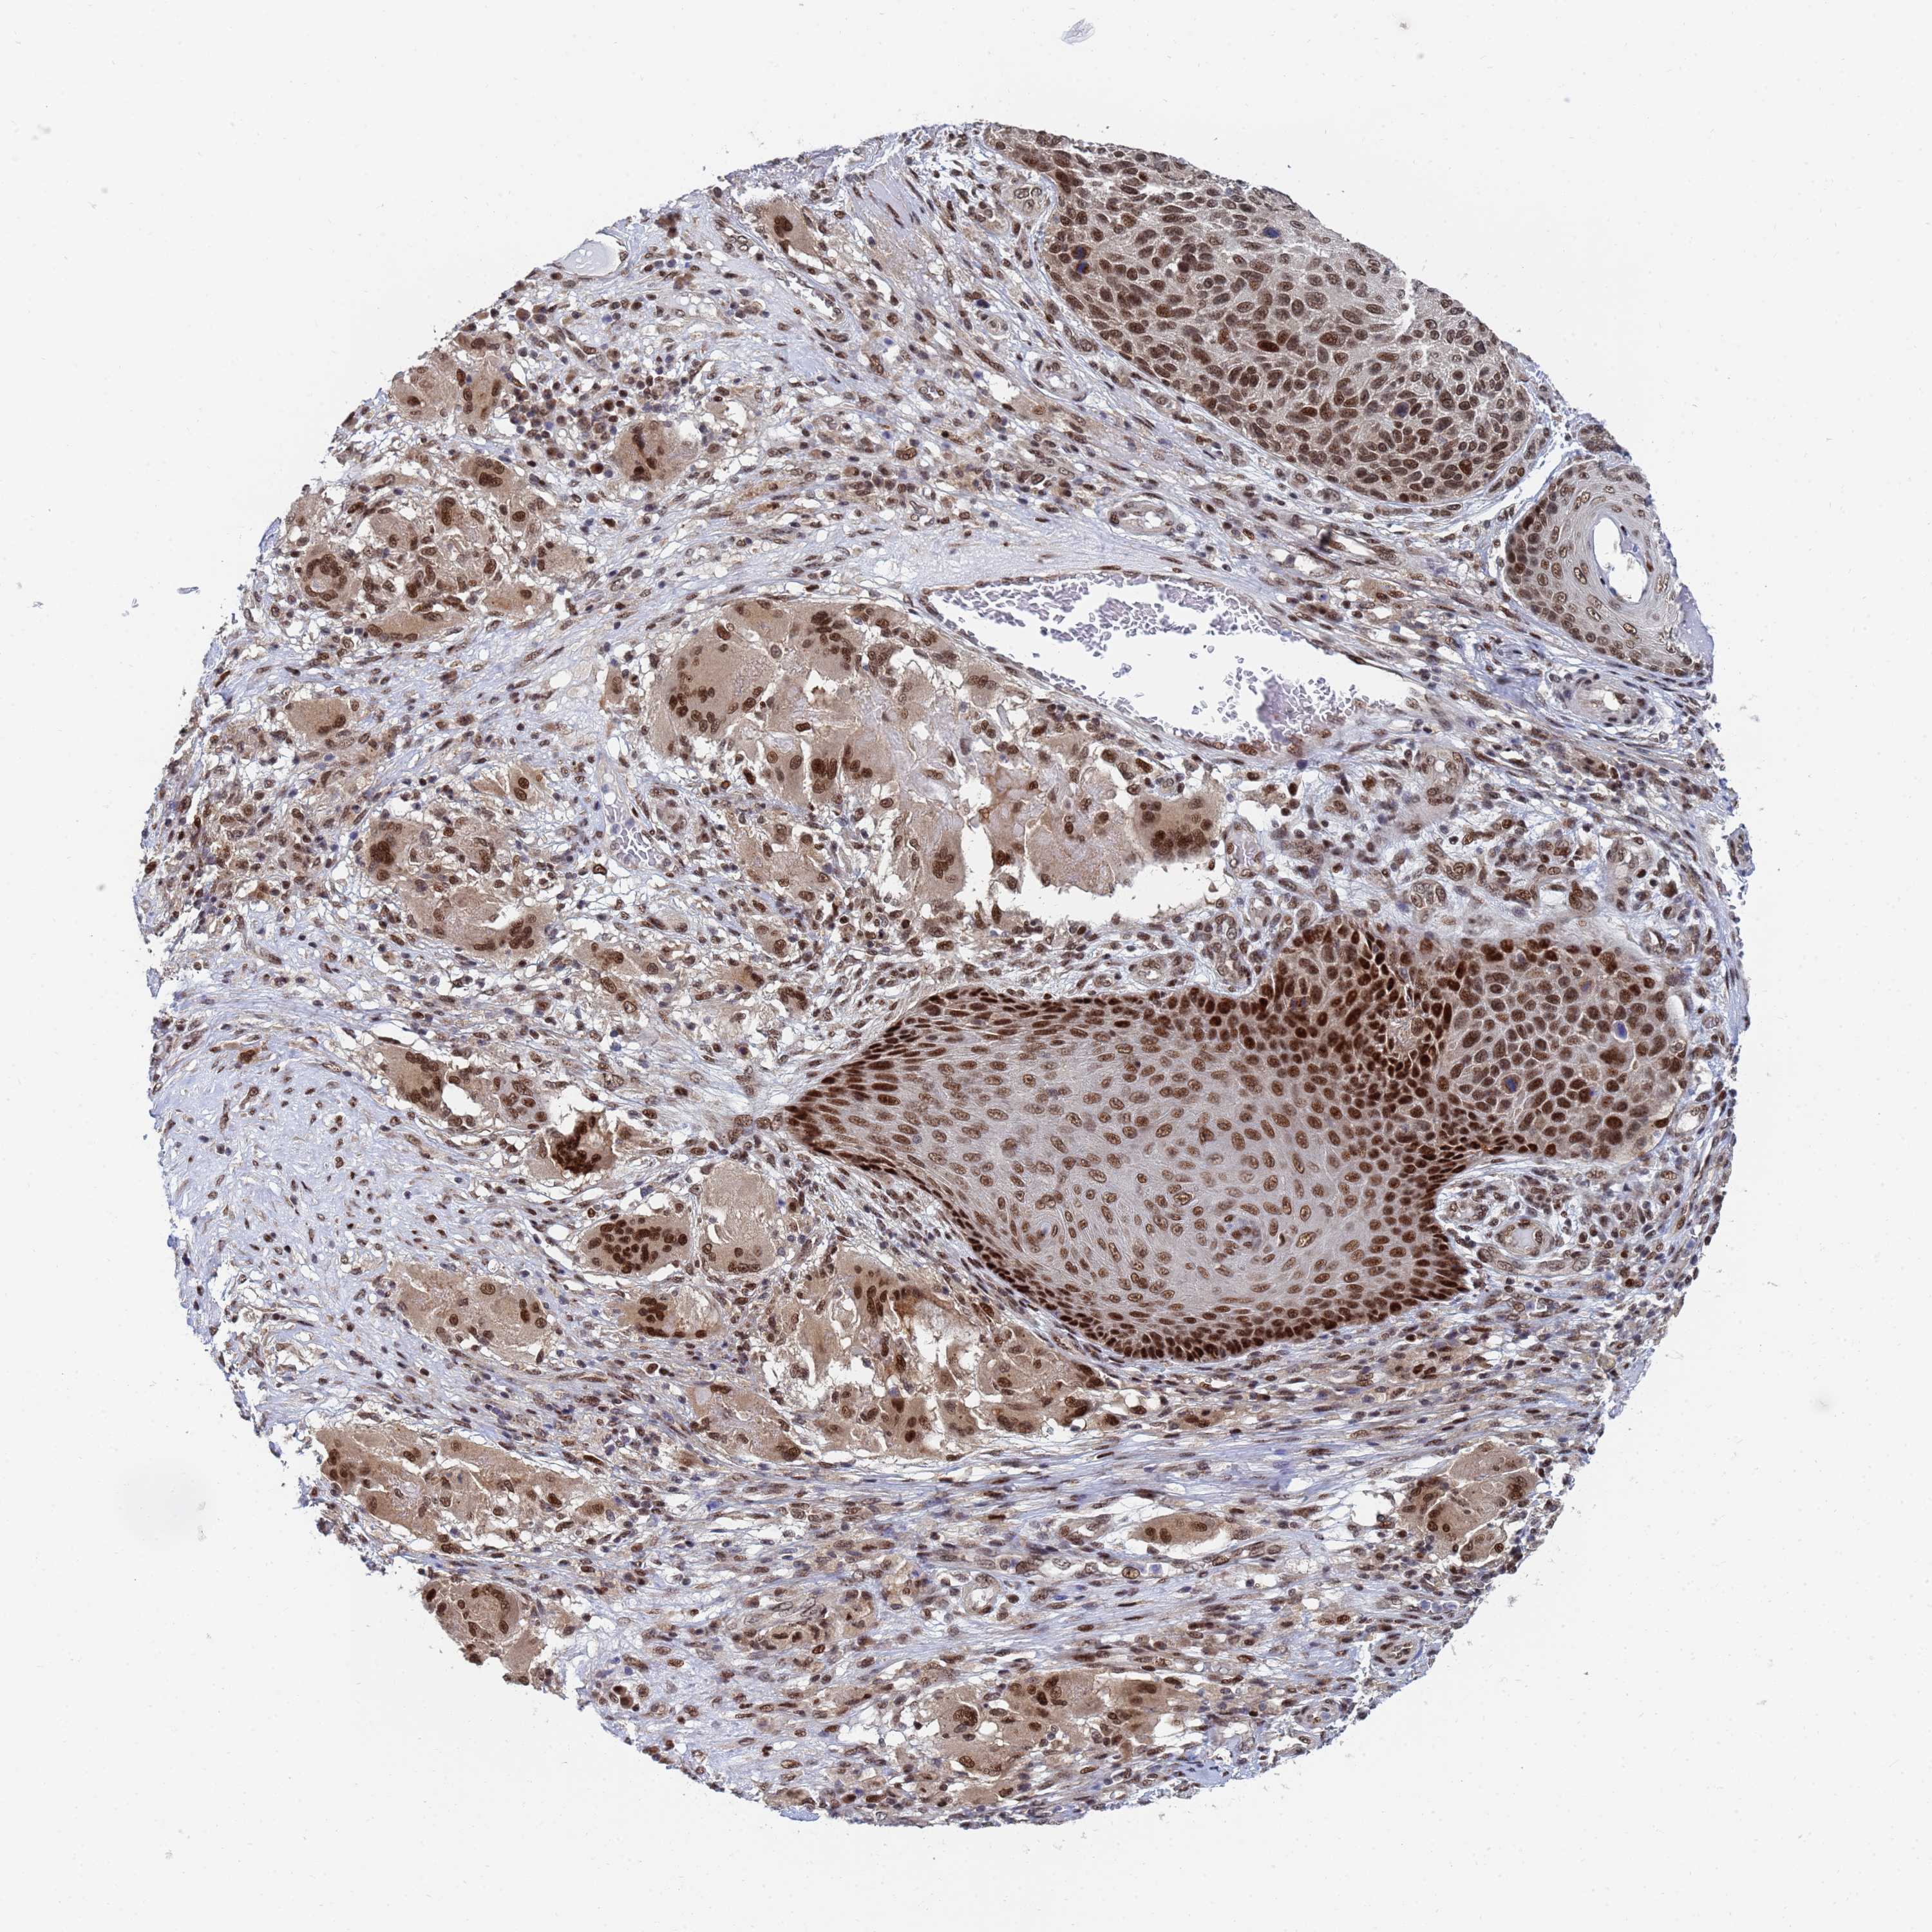

SKIN CANCER - Protein expressioni

A mouse-over function shows sample information and annotation data. Click on an image to view it in a full screen mode. Samples can be filtered based on level of antibody staining by selecting one or several of the following categories: high, medium, low and not detected. The assay and annotation is described here.

Each image is clickable and will lead to virtual microscopy that enables deeper exploration of all samples and also displays staining intensity scores, fraction scores and subcellular localization as well as patient and tissue information for each sample.

Antibody HPA035693

Staining

High

Intensity

Strong

Quantity

>75%

Location

Nuclear

Squamous cell carcinoma, NOS